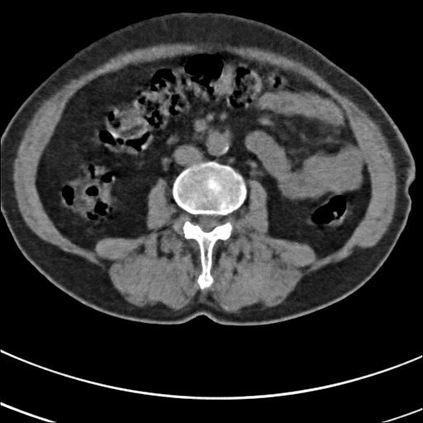

Low-Dose Computed Tomography (LDCT) technique, which reduces the radiation harm to human bodies, is now attracting increasing interest in the medical imaging field. As the image quality is degraded by low dose radiation, LDCT exams require specialized reconstruction methods or denoising algorithms. However, most of the recent effective methods overlook the inner-structure of the original projection data (sinogram) which limits their denoising ability. The inner-structure of the sinogram represents special characteristics of the data in the sinogram domain. By maintaining this structure while denoising, the noise can be obviously restrained. Therefore, we propose an LDCT denoising network namely Sinogram Inner-Structure Transformer (SIST) to reduce the noise by utilizing the inner-structure in the sinogram domain. Specifically, we study the CT imaging mechanism and statistical characteristics of sinogram to design the sinogram inner-structure loss including the global and local inner-structure for restoring high-quality CT images. Besides, we propose a sinogram transformer module to better extract sinogram features. The transformer architecture using a self-attention mechanism can exploit interrelations between projections of different view angles, which achieves an outstanding performance in sinogram denoising. Furthermore, in order to improve the performance in the image domain, we propose the image reconstruction module to complementarily denoise both in the sinogram and image domain.